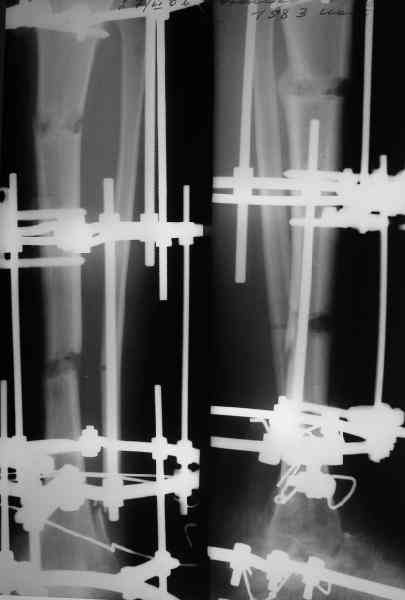

Очень интересное наблюдение. Хотел спросить позволяет-ли примененный тип фиксации не использовать внешней шины. На правой послеоперационной рентгенограмме (кажется) просматривается таковая. Если необходима наружная иммобилизация, как долго?

Аппарат был снят окончательно только после введения стержня, то есть оставалось по одной спице в проксимальном и дистальном метафизах большеберцовой кости, спицы в пятке. Фото во время рассверливания в приложении.

Стержень 12 мм, винт диаметром 6 мм, костная трубка вокруг хорошая. Перелом такого винта пока не наблюдали ни разу на нескольких сотнях

пациентов.